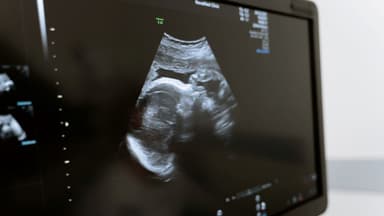

Độ dày bánh nhau là một phép đo siêu âm phổ biến, được thực hiện bằng cách đo khoảng cách vuông góc từ màng đệm đến thành tử cung ở chiều lớn nhất.

Nhìn chung, tiến trình phát triển của độ dày bánh rau theo tuổi thai diễn ra tương đối đồng đều và mang tính tuyến tính. Trên hình ảnh siêu âm, tốc độ tăng trưởng trung bình của bánh nhau là khoảng 1mm mỗi tuần.